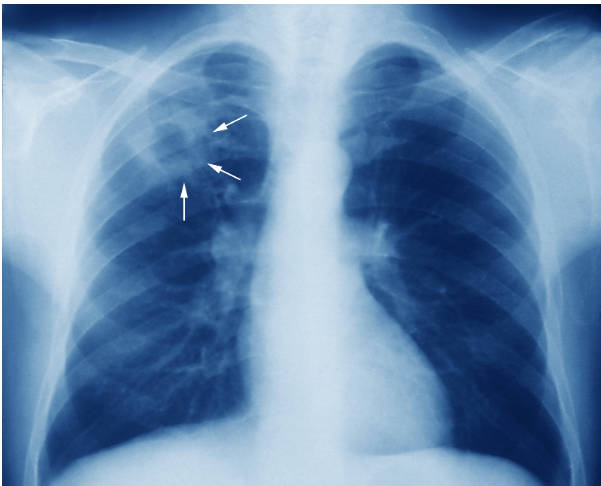

- Phương pháp cận lâm sàng: Phương pháp xác định ban đầu là xét nghiệm đờm AFB. Tuy nhiên tùy vào giai đoạn tiến triển bệnh mà kết quả sẽ khác nhau hoặc bệnh nhân (HIV) đã từng điều trị bằng các thuốc ảnh hưởng đến vi khuẩn lao. Nuôi cấy vi khuẩn lao cũng gặp nhiều khó khăn và mất nhiều thời gian (4 - 12 tuần), do đó, chụp X-quang phổi được đề xuất thêm hoặc thử phản ứng với lao tố trên da. Trường hợp xét nghiệm tìm BK không cho kết quả, phản ứng khuếch đại gen được thay thế bởi độ nhạy và đặc hiệu, cho kết quả nhanh.

- 1 mẫu tiêu bản AFB (+) và trên X-quang cho thấy hình ảnh lao tiến triển.

- 2 lần xét nghiệm đờm AFB (-) và trên X-quang cho thấy hình ảnh lao tiến triển. Xét nghiệm được thực hiện cách nhau 3 tuần, mỗi lần lấy 3 mẫu đờm.